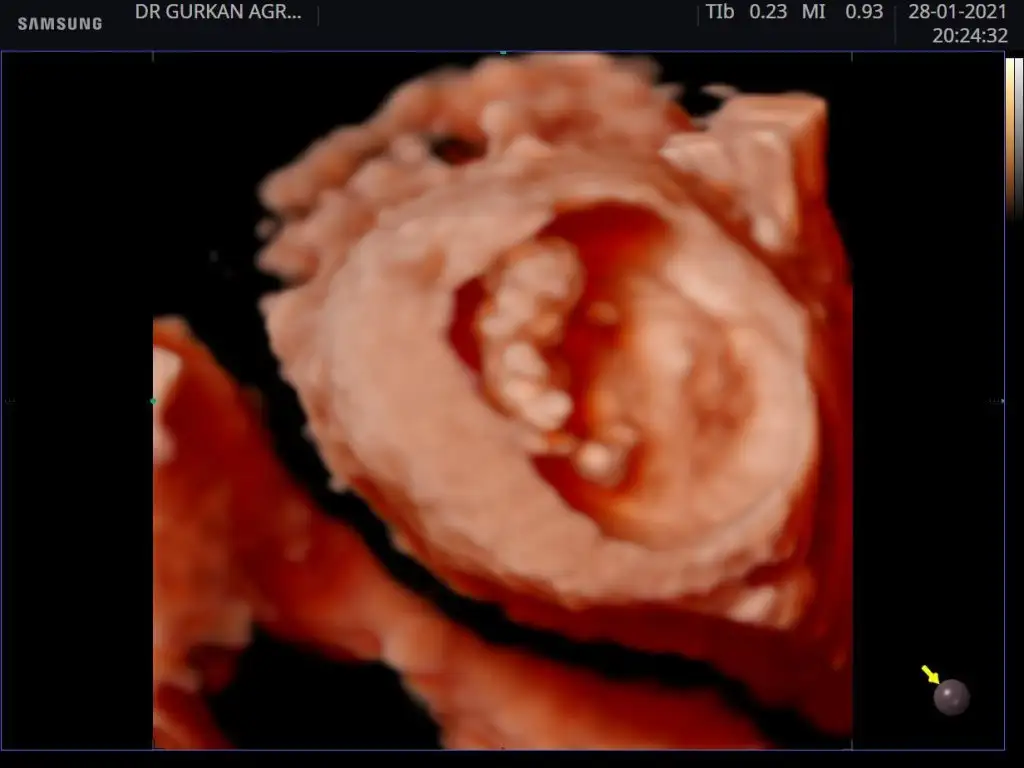

Nub teorisindeki çıkıntıdan baktı tutma ihtimali yüksek oluyor bazen yanılma payı olabiliyor bende olmamıştı senin nub teorisinde bebeğin kızNerden anladınız herkes erkek diyor

Tabiki Allah bilir. Ben ne doktorum nede uzman ben nub teorisine göre tahminde bulunuyorum benim yaptigimi herkes yapar tabiki sadece Rabbim bilir herseyi!Rabbim gönlünce versin inşallah bunlar teoriden ibaret doktorlar bile yanılıyor benim 2 yıl önce arkadaşım kız bebeğe hamileydi doğumda şok yaşadılar bebek erkekti çok gülmüştük kız bekledikleri için herşey pembeydi sonra pembiş pembiş giydi belli süre herşeyi rabbim bilir